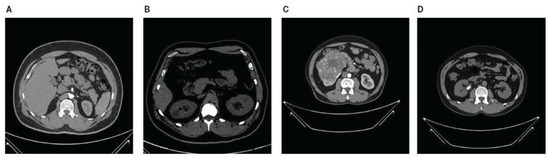

Nazmul Islam and Humaion Kabir [24] compiled the CT kidney dataset using the picture archiving and communication system (PACS) from several hospitals in Dhaka, Bangladesh. Some hospitals in Dhaka serve a wide variety of urban communities. Given that Dhaka is a highly populated and culturally diverse city, the dataset probably includes people from different socioeconomic statuses, enhancing its ability to represent urban patients in Bangladesh. This dataset includes images of patients with normal kidneys, tumors, stones, or cysts. The dataset includes coronal and axial cuts from both non-contrast and contrast urogram and abdomen CT scans, totaling 12,446 images—normal: 5077 CT images; cyst: 3709 CT images; stone: 1377 CT images; and tumor: 2283 CT images. Each CT image was sized 512 × 512 pixels. The dataset can be found on Kaggle, and its class distribution is shown in Table 3. The CT images were originally in DICOM format but were converted to JPEG using the Sante Dicom tool. The CT images were annotated using the Philips IntelliSpace Portal application and were double-checked by a medical professional and technician to ensure accuracy. Figure 1 depicts a sample of CT images from this CT kidney dataset.

In our experiment, we considered ethical matters. While the dataset description does not explicitly mention ethical approvals or consent, it is generally understood that open-source datasets comply with ethical guidelines. Consent for the use of de-identified data is typically obtained from patients during the data collection phase. For datasets collected and shared on platforms like Kaggle, the responsibility for ensuring compliance with privacy regulations usually falls on the data provider.